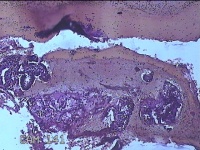

宫腔内容物

性别

女

年龄

35岁

临床诊断

人流不全

一般病史

人流术后41天。

标本名称

大体所见

灰白暗红色不规则碎组织1.8x1.5x0.3cm一堆,未发现明显的绒毛样组织。